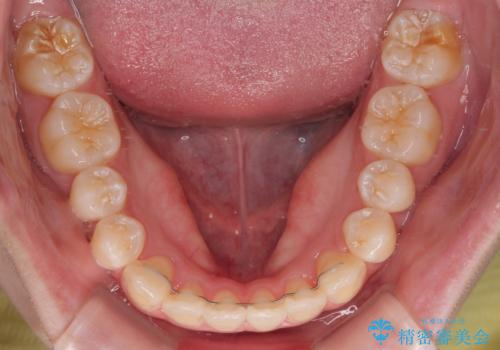

患者様の協力もあり、およそ1年間で治療を完了。スムーズな歯の移動を実現しました。

上下の正中(真ん中のライン)もずれることなく、バランスの取れた美しい歯並びに。笑顔に自信を持てる仕上がりとなりました。

「もっと時間がかかると思っていましたが、あっという間でした。装置も思ったより気にならず、前歯がきれいに並んでとても満足しています。」とうれしいお言葉をいただきました。